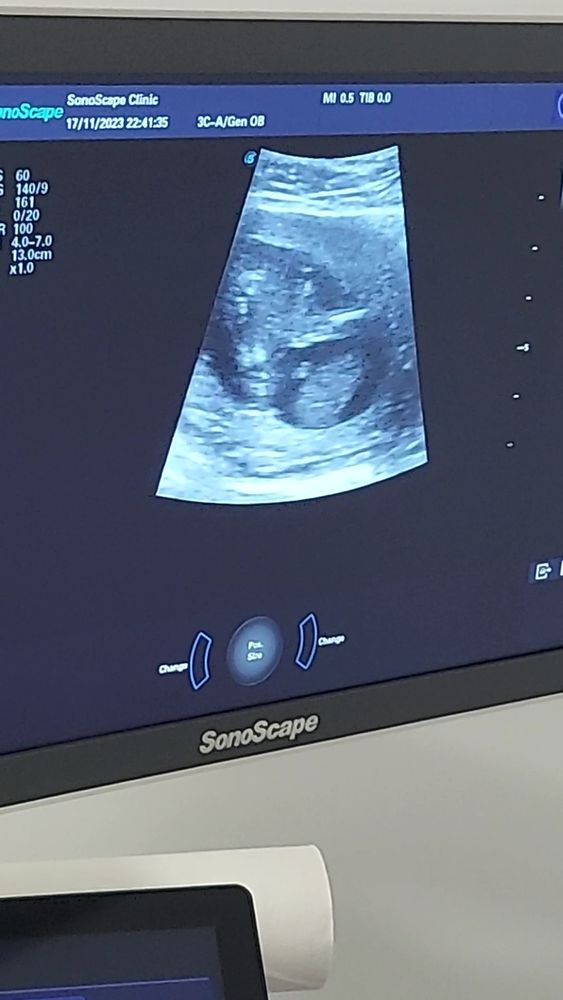

Сегодня узнаем кто в домике живет) (много фото узи) а вы как думаете?)

Плохое качество фото, видно что все они сняты между ног, но не чётко, вообще яичек нет вроде бы, значит девочка.

УЗИ 12 недель Точно девочка?)